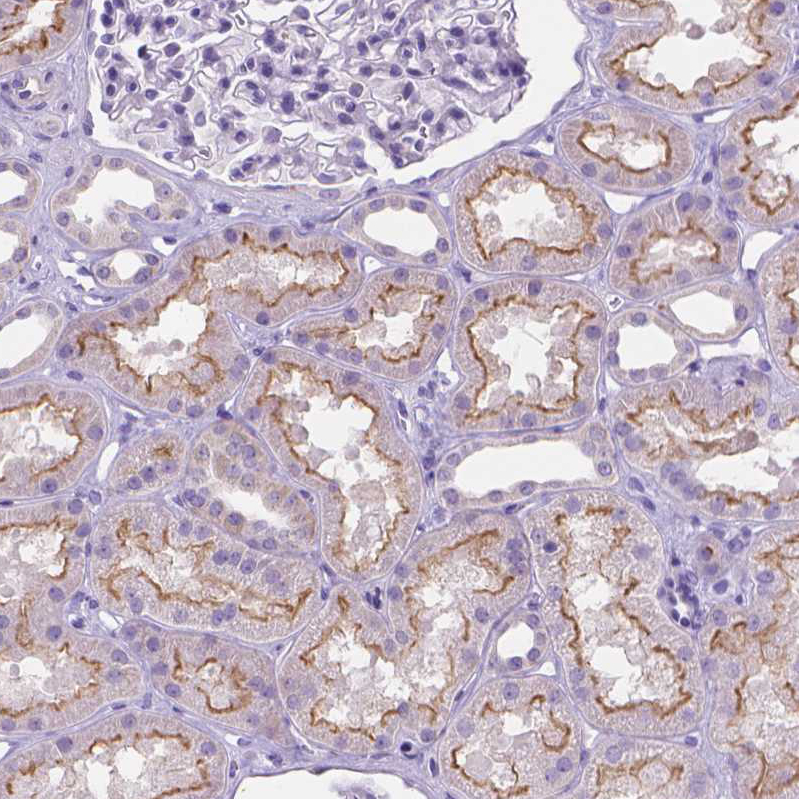

Immunohistochemical staining of human endometrium shows moderate membranous positivity in a subset of glandular cells.